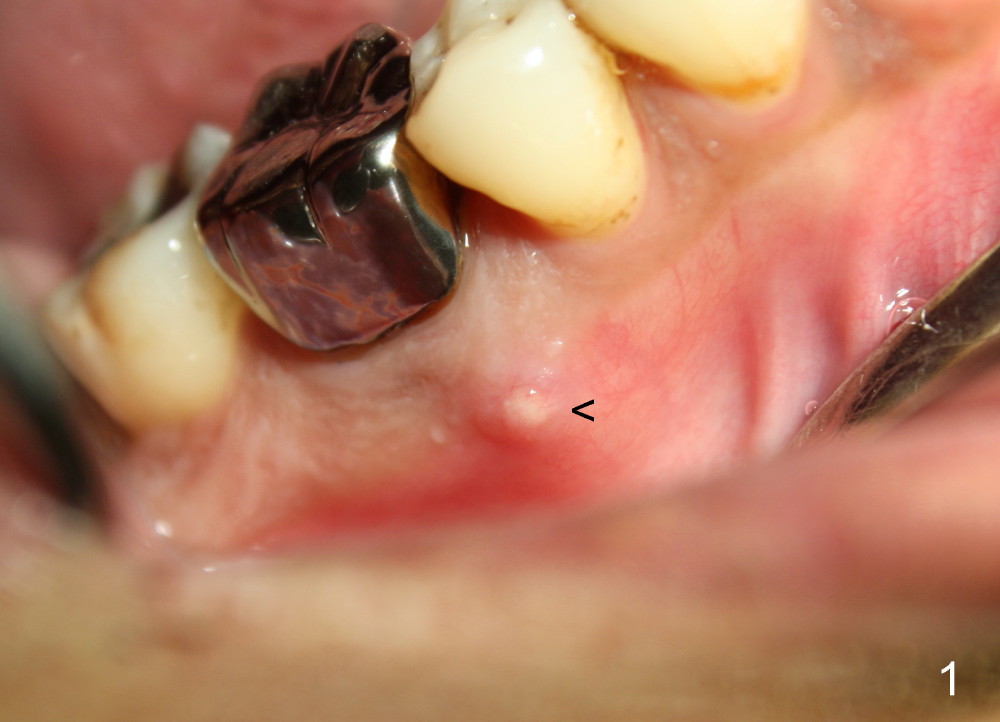

The patient returns for extraction and immediate implant after 7 days of oral Amoxicillin. There is a deep pocket mesiolingually in addition to the mesiobuccal fistula (Fig.1 <). The metal crown and then the tooth are sectioned. The crack of the mesial root is confirmed during extraction. The coronal portion of the mesiobuccal plate is defective, corresponding to the fistula. Both the mesial and distal sockets are large with a thin septum in between. Osteotomy is established at the base of the septum, slightly toward the mesial socket, as evidenced by a 5x20 mm tap in place (Fig.2). Finally, a 7x17 mm implant is placed (Fig.3 I; A: abutment; G: bone graft). The insertion torque is more than 60 Ncm.